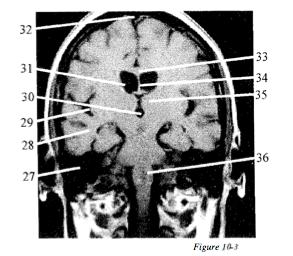

Question 3

Question

Label with the letters: AA. Third ventricle, BB. Septum pellucidum, CC. Superior sagittal sinus, DD.Thalamus, EE. Lateral ventricle, FF. Temporal lobe, GG. Sylvian fissure, HH.Pons, II. Petrous ridge, JJ. Corpus callosum

Answer

• II

• FF

• GG

• AA

• EE

• CC

• JJ

• BB

• DD

• HH